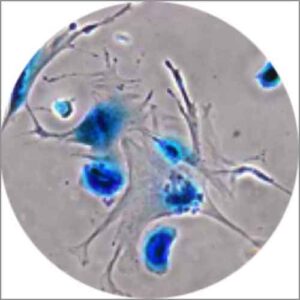

Ecco il 'trucco che invecchia' le cellule tumorali e le fa morire inesorabilmente: si tratta di attivare il processo di...